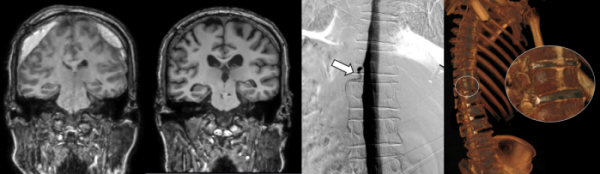

이번에 치료를 받은 뇌척수액 정맥 누공이 있던 환자 4명 모두는 세브란스병원에 오기 전 뇌압이 낮아져 두통이 생기는 ‘자발성 두개내 저하증’이 의심됐으나, 척추 MRI와 단순 척수 조영술 검사에서는 전부 정상 소견을 보였다.

세브란스병원은 최근 디지털 감산 척수조영술(DSM)을 국내 최초로 도입해 이와 같은 기존 진단법의 한계를 극복했다. DSM은 척수에 조영제를 주입하고 모니터 화면으로 뇌척수액의 흐름을 실시간으로 확인할 수 있다. 이를 통해 뇌척수액이 새나가는 구멍을 정확하게 찾아낼 수 있게 됐다.

DSM과 더불어 세브란스병원이 함께 진행 중인 측위 컴퓨터단층촬영(CT) 척수 조영술까지, 모두 뇌척수액 정맥 누공을 진단할 수 있는 최신 기법이다. 신경과 전문의(주민경, 하우석 교수)와 신경외과 전문의(하윤 교수)가 긴밀히 협력하는 만큼 진단과 치료가 원스톱으로 가능하다.

이번에 세브란스병원을 찾은 환자들은 DSM 검사와 측위 CT 척수 조영술로 뇌척수가 새어나가는 부위를 정확히 진단‧치료받고, 뇌압을 회복했으며 경막하출혈도 사라졌다. 이에 따라 환자들이 보였던 인지기능 저하와 보행장애도 모두 호전됐다.